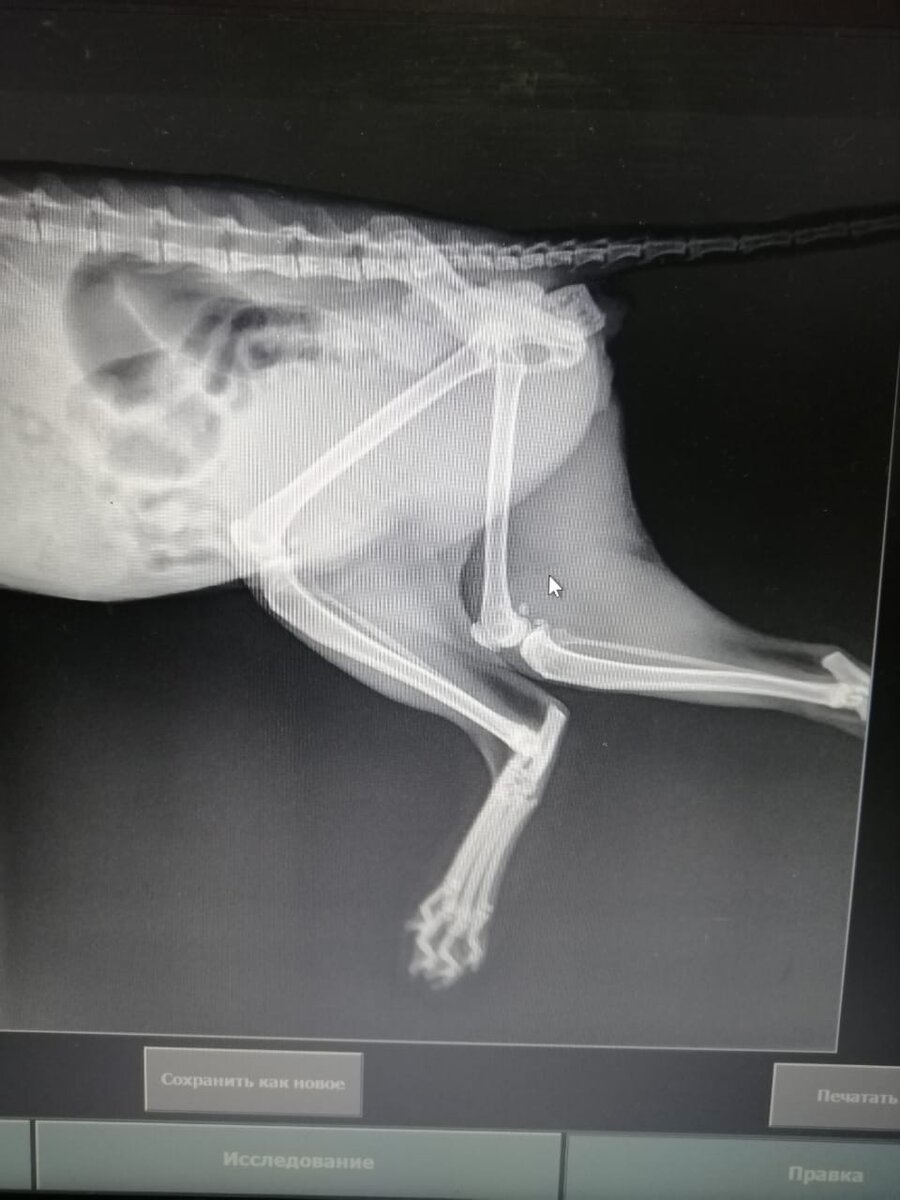

Что ж так не везет нашим подопечным?😢 Беляш... Мотя... Друзья, простите за обман... Мы не сможем спасти Мотю ни вместе, ни по отдельности😭 Когда уже люди начнут понимать, что уличная жизнь животных не проходит для них бесследно... Мотю вчера осмотрели специалисты. Лапка у Моти была вывихнута с растяжением связок и защемлением седалищного нерва😫. Лечение: пока массаж, физио и уколы. Небольшая положительная динамика есть. Но прогнозов не дают. Т. к. уже началась атрофия😫. Если бы в первый день обратились, то шансов было бы больше. Опухоль на молочной железе не операбельная, она с прорастанием в грудную кость😭. Метастаз пока явных нет. А судя по ее одышке, врачи предполагают, что они есть уже и в легких. Лечения нет!!! Операция только растревожит😫. Даже биопсию не стали делать, чтобы не запустить дальнейший быстрый рост опухоли. Химия в данном случае - просто издевательство🥺. Т. к. результатов не принесет, а на общем состоянии скажется отрицательно. Несколько дней еще полечат у Мо